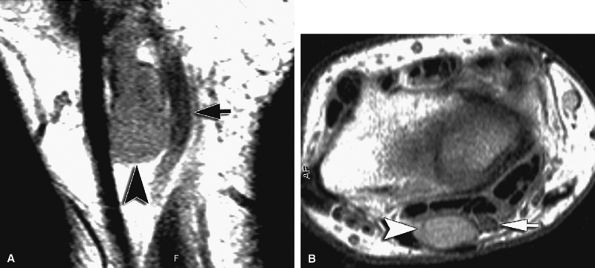

![]() |

FIGURE 12.21 ● Anconeus epitrochlearis muscle. Axial T1-weighted image demonstrates the accessory muscle (white arrows) effacing the fat within the cubital tunnel. The ulnar nerve (black arrow) is normal. O, olecranon.